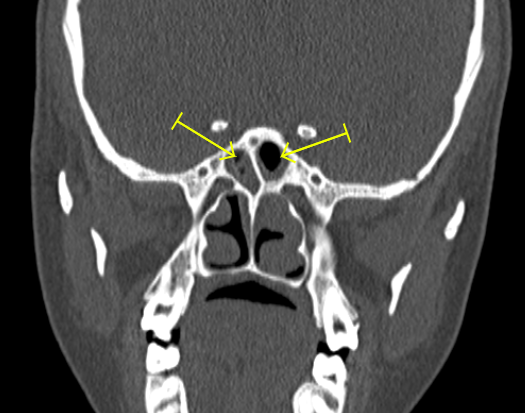

Hypertrophied nasal turbinates l Bilateral maxillary l ethmoidal and sphenoidal sinusitis

Hypertrophied nasal turbinates coronal view